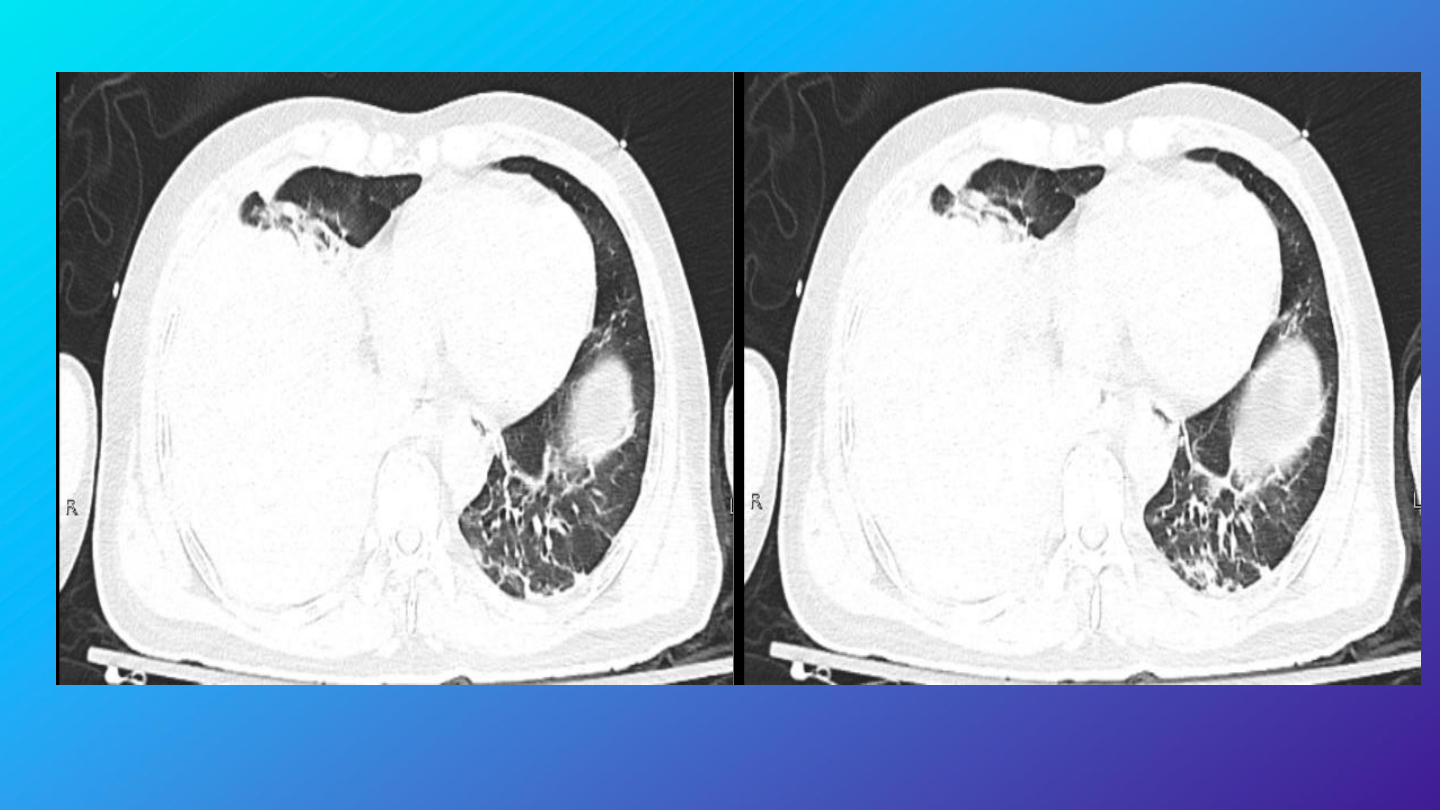

完善胸部增强

右侧胸腔积液、积血,较前片

2024-10-22 10:20

)积液、积血

增多,请结合临床;

右肺下叶肺不张,右肺各叶及左

肺下叶炎性渗出改变。

右侧第

5

6

前肋骨皮质略褶皱。